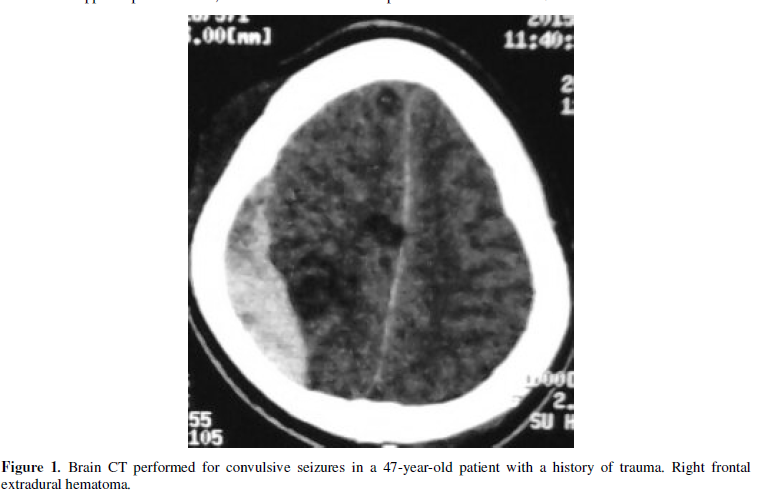

such as sequelae pathologies and traumatic pathologies were found in our study.

Neishige [16] in Japan reported several

cases of subdural hematoma as a cause of seizures. In our study it is rather extradural

hematoma. We agree with Duffour et al. [17]

who described a case of seizures in connection with an extradural hematoma of

vertex in a 36-year-old woman. Sequelae pathologies encountered in our study